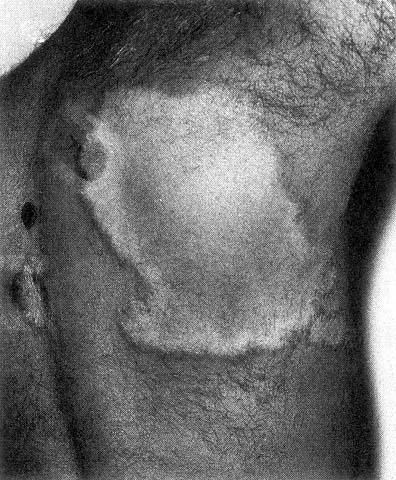

TUBERCULOID LEPROSY

Tuberculoid leprosy (TT) - few skin lesions.

Tuberculoid leprosy is characterised by restricted growth of the pathogen and high cell-mediated immunity.